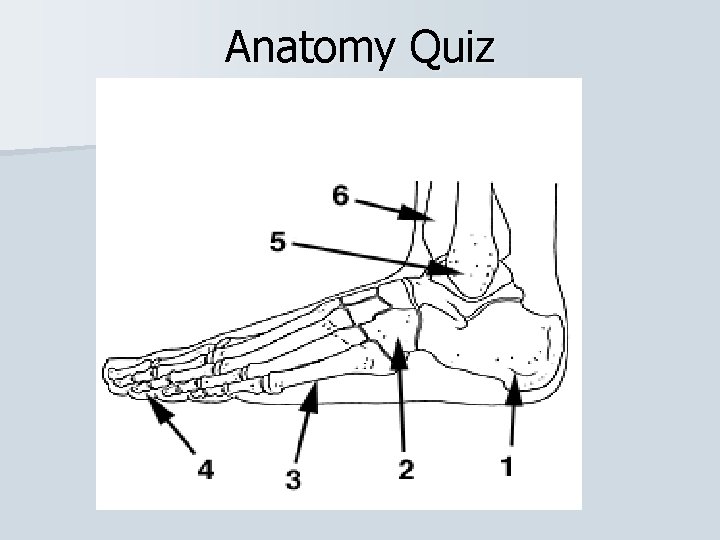

Bones of the Ankle and Foot

Anatomy Quiz